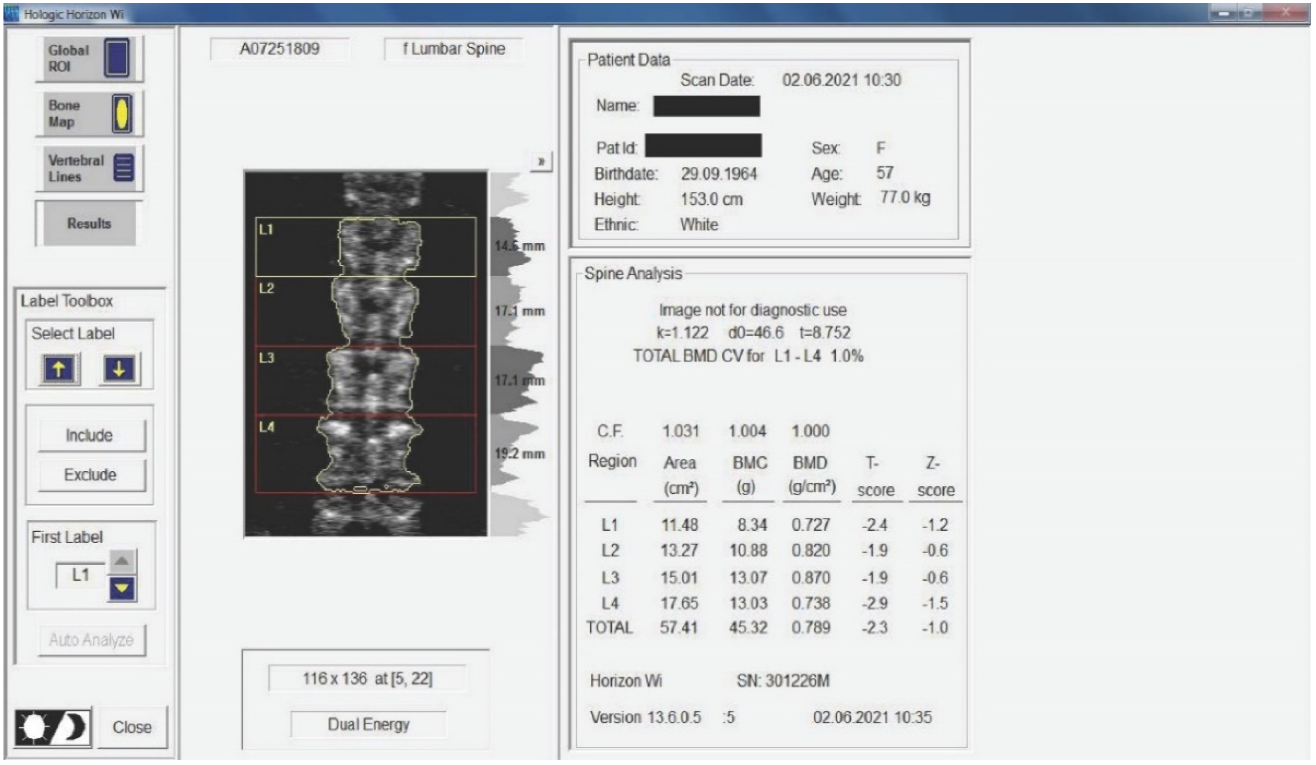

Twenty-nine non-smoking women with postmenopausal osteopenia/osteoporosis, a body mass index (BMI) of ≤25, and no physical exercise contraindications were included in the study. The subjects had not participated in any exercise program in the last 3 months, and all of them were sedentary people (less than 60 min of exercise per week). BMD was measured using DEXA analysis (Hologic Horizon, Santa Clara, CA, USA) and radiological examination (see Figure 1 and Figure 2). Skeletal BMD can be measured using DEXA, which is considered by some authors to be one of the most effective methods of diagnosing osteoporosis or osteopenia [8]. Currently, DEXA is the standard reference for diagnosing osteoporosis [9,10]. It is a precise evaluation method that involves exposing the areas to be evaluated to a small amount of X-rays and allows the areas of interest to be objectively measured. In this method, the two X-rays are absorbed differently in the bone, and the BMD is calculated in g/cm2 using simultaneous equations. Among the results offered by DEXA investigation is some information on bone mineral content (BMC) given in g, area measured in cm3, and BMD given in g/cm2 [11]. The measurement was compared with two reference values: one for young adults (30 years, which gives a T-score) and one for people of the same age as the evaluated person (which gives a Z score) [12]. DEXA has certain strengths, such as not exposing the patient to a high dose of radiation (1–6 μSv) and having a short time scan (1–2 min). Following the DEXA investigation, the software recorded the values obtained and displayed them on the screen. The T-score obtained by the subject being examined refers to her bone mass, taking as reference an individual of the same gender with peak bone mass. A classification was established depending on the score obtained: normal bone mass density (score between −1 and 0 or higher), osteopenia (between −1.1 and −2.4), and osteoporosis (a score of −2.5 or less). The Z score obtained refers to the BMD of the scanned subject compared with a subject of the same age and weight (see Figure 2).

Medical investigations (DEXA and radiographs) were conducted by a technician and the radiographs was interpreted by a specialist. The T-score provided information on whether the subject could be included in the study (the condition being that the subjects had osteopenia or osteoporosis), and the lumbar spine BMD was the quantitative information we used to make pre- and post-test comparisons. Table 1 and Table 2 and Figure 2 present information on BMD in each vertebra, but the last and the most important result is the total BMD, which is the reference result. With the help of radiography, we used visual information about the body and height of the vertebrae, the presence or absence of vertebral fractures, and the height of the intervertebral spaces. We could also observe if the subject had a history of other pathologies that would be a contraindication to performing the training protocol. Different from the DEXA investigation, which was made at the beginning and at the end of the study, the X-ray was used only at the beginning of the study to rule out the possibility of other pathologies in the lumbar area that could prevent the subjects from participating in the program.

Figure 2. Measurement of BMD for the subjects included in the study. The results are displayed planimetrically, relating the BMC to the surface being evaluated (g/cm2). This also gives us a total T-score expressing whether the person has normal BMD (T-score between −1 and 0 or above), osteopenia (T-score between −1.1 and −2.4), or osteoporosis (T-score of −2.5 or less). The results in the image show us that the subject has osteopenia (but is extremely close to osteoporosis).